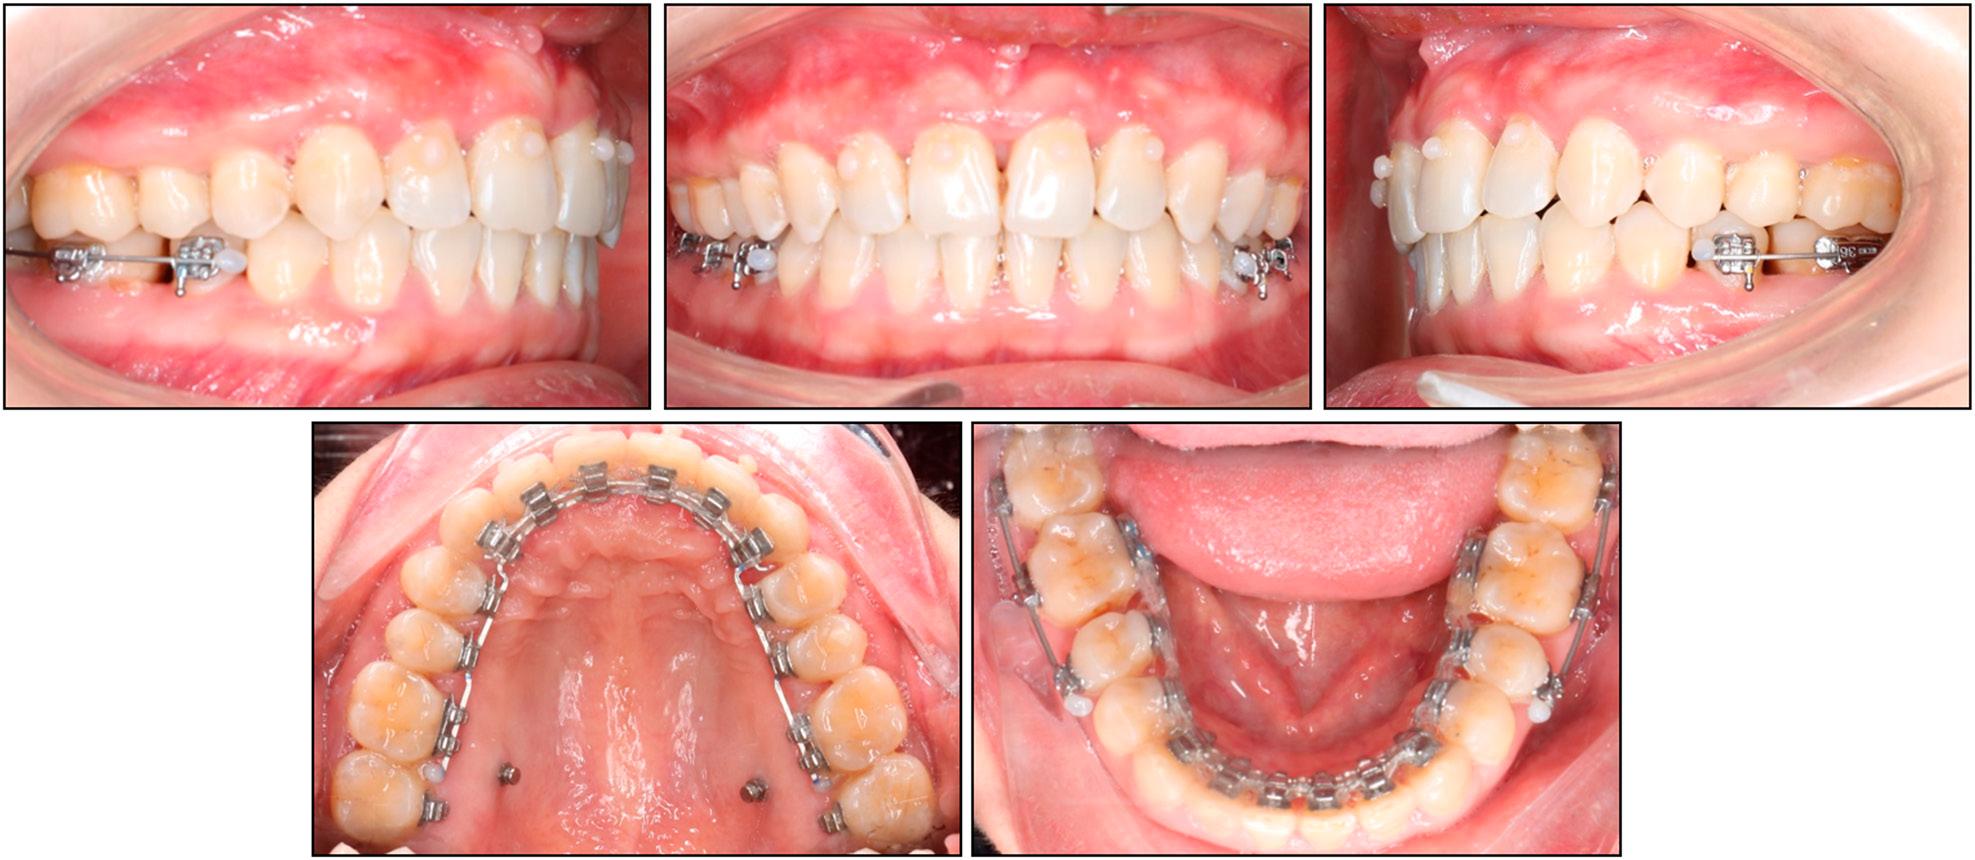

The cephalometric analysis showed a skeletal Class II relationship with a slightly retruded mandible and a protruded maxilla (SNA: 85.5°, SNB: 75.8°, ANB: 9.7°). The vertical skeletal pattern indicated a slight hypodivergence (FMA: 21.4°). The upper incisors were excessively retroclined (U1/SN: 73.9°) while the lower incisors were proclined (IMPA: 103.4°). The upper incisal display was slightly increased (3.7 mm). The upper lip was slightly protruded but the lower lip was normally placed (upper lip to E-line, 1.9 mm; lower lip to E-line, 0.2 mm) (Table II). The panoramic radiograph indicated the presence of all teeth, excluding the mandibular left third molar (Figure 10).

Case 2: initial panoramic and cephalometric radiographs and tracing.